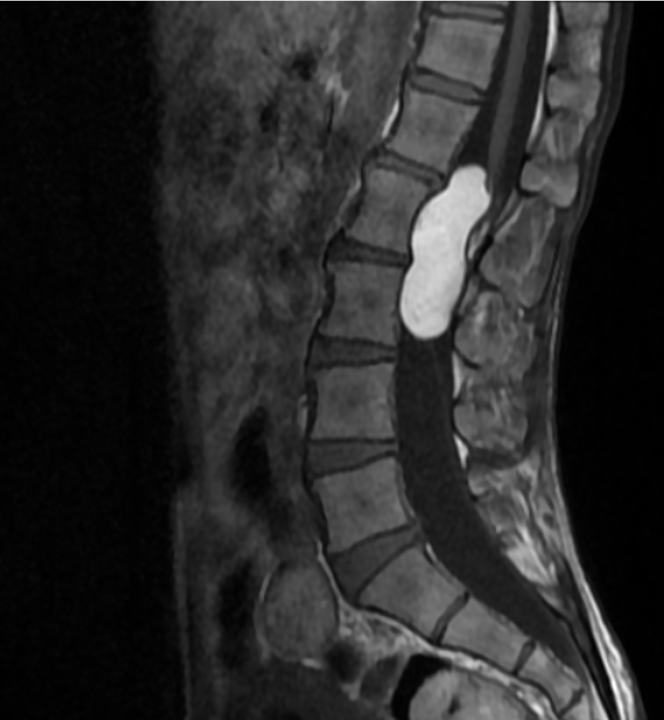

SAGITTAL T1

MRI is the modality of choice for evaluation of spinal epidermoid cysts. Although classically described as T1 hypointense, T2 hyperintense lesions with diffusion restriction, imaging appearances may be variable, particularly in chronic or protein-rich lesions.

In the present case, the lesion demonstrates T1 hyperintensity and T2 hypointensity, an atypical appearance attributed to dense keratinaceous debris, cholesterol crystals, high protein concentration, and chronic desiccation, resulting in shortening of T1 and T2 relaxation times. Such lesions are described as atypical or “white” epidermoid cysts.

Post-contrast imaging shows no significant internal enhancement, supporting a non-neoplastic cystic etiology.

Associated scalloping of the lumbar vertebral bodies reflects chronic, slow-growing mass effect, further supporting the benign and indolent nature of the lesion.